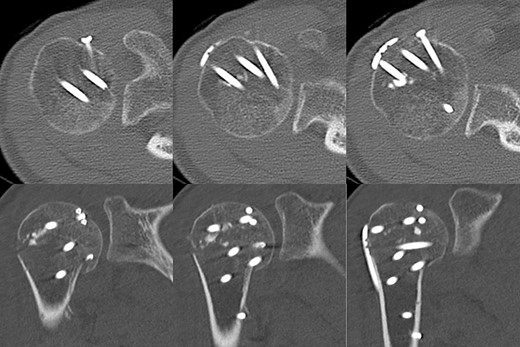

A 39-year-old man was transported via ambulance after being hit by a car. The radiographs revealed a one-part proximal humeral fracture with displacement at the surgical neck (Fig. 1). However, computed tomography (CT) revealed humeral head impression fracture and lesser tuberosity fracture in addition to a surgical neck fracture (Fig. 2). In addition, 3D-CT revealed that the collapse occupied approximately 20% of the articular surface with no glenoid defect (Fig. 3). Therefore, we first performed arthroscopic-assisted reduction and internal fixation of the humeral head impression fracture, followed by open reduction and internal fixation (ORIF) of the proximal humeral fracture.

Original CT scan showing impression fracture and surgical neck fracture.

3D-CT scan showing approximately 20% of articular surface of the right proximal and no glenoid defect, indicating no posterior shoulder dislocation.

Postoperative radiographic and CT evaluations showed reduced fractures on the humeral head and surgical neck (Fig. 7). At 24 months of postoperative follow-up, radiographic and CT evaluations showed no signs of osteoarthritis or reimpression (Fig. 8). Two years after the primary surgery, we performed implant removal at the patient’s request (Fig. 9). When performing implant removal, we additionally performed a second-look evaluation with arthroscopy to assess the degree of healing in the joint. We noted no impression or exposure of cartilage callus on either side of the humeral head or glenoid (Fig. 10).

Postoperative X-ray and CT scan showing sustained anatomical reconstruction of articular surfaces and no signs of osteoarthritis.

Two years later, pre-implant removal CT showed that the reduction in the depressed surface had been maintained with no obvious arthritic changes.